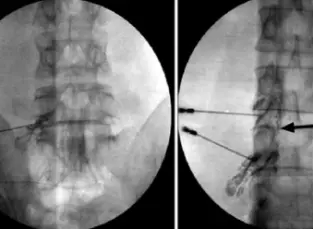

It is vital for managing discogenic pains in the back and neck. Intra-articular steroid for facet pains, RF ablation and caudal epidural also require fluoroscopy.